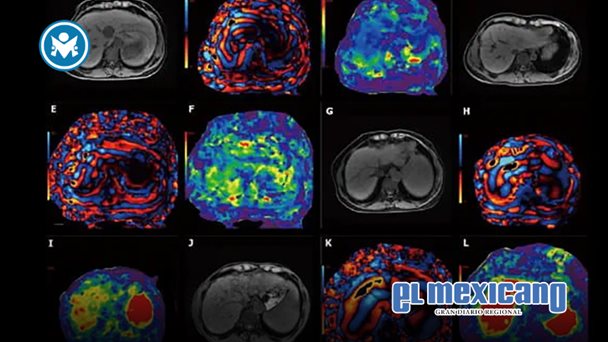

A diferencia de una resonancia magnética abdominal completa, que captura una amplia gama de estructuras abdominales y suele requerir el uso de medio de contraste, el hepatograma MASLD se enfoca únicamente en el contenido de grasa y la rigidez del hígado. Para ello, se apoya en dos técnicas clave: la cuantificación de grasa por resonancia magnética y la elastografía por resonancia magnética, que utiliza ondas mecánicas suaves para medir la rigidez hepática, un indicador directo de fibrosis.

"Es, esencialmente, un examen diseñado a la medida", comenta el Dr. Nakul Gupta, radiólogo diagnóstico en el Hospital Houston Methodist, quien desarrolló el nuevo protocolo junto al Dr. Victor. "Lo redujimos a las secuencias esenciales que responden a una pregunta muy específica: ¿este paciente padece o no fibrosis hepática esteatósica?".